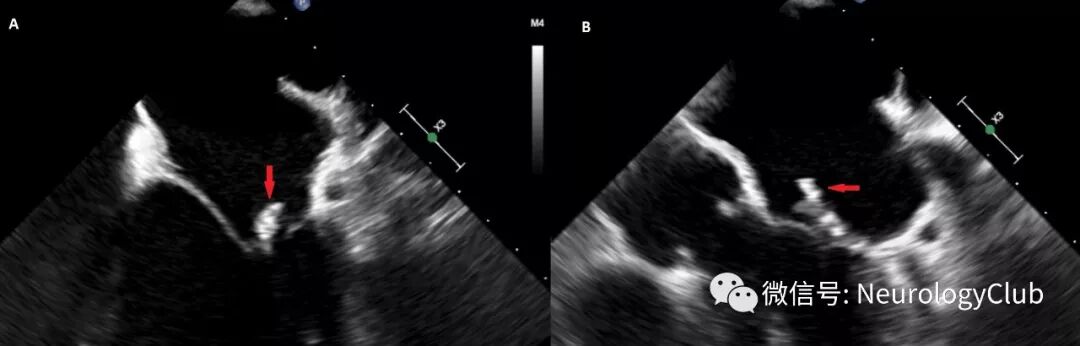

(图1:A:最初的头颅CT平扫可见凸面蛛网膜下腔出血内高密度病灶;B:额叶血管内可见2处高密度病灶)

(图3:A:经食道心超提示二尖瓣赘生物;B:经食道心超提示二尖瓣赘生物内可见钙化

患者表现为凸面蛛网膜下腔出血伴出血区和动脉内小钙化灶(图1)。进一步查体可闻及新发较响的收缩期杂音。给予经验性抗感染性心内膜炎治疗。4小时后患者症状恶化,出现表达性失语。复查影像学可见新发钙化病灶和缺血性卒中(图2)。超声心动图提示二尖瓣赘生物伴钙化(图3)。血培养可见副血链球菌生长。